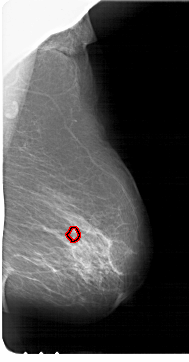

FILE: A_1729_1.RIGHT_CC.OVERLAY

TOTAL_ABNORMALITIES 1

ABNORMALITY 1

LESION_TYPE CALCIFICATION TYPE PLEOMORPHIC DISTRIBUTION CLUSTERED

ASSESSMENT 4

SUBTLETY 3

PATHOLOGY MALIGNANT

TOTAL_OUTLINES 1

BOUNDARY